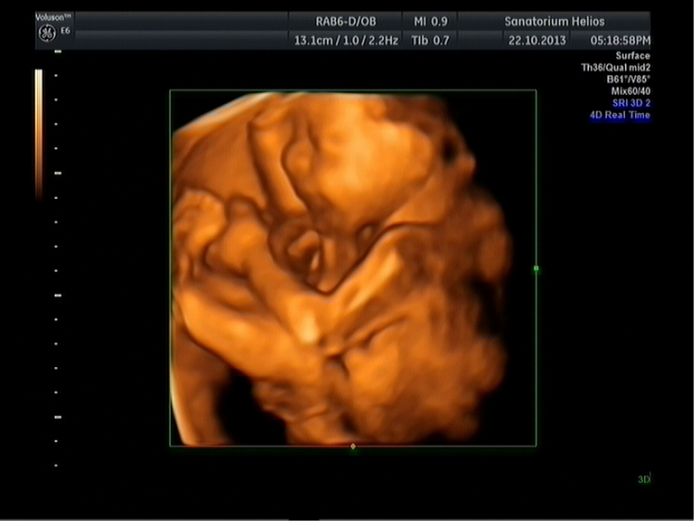

.TP se mi posunul z 25.1. na 18.1.Byla jsem na 3D,bylo to supr.Potvrdili nám chlapečka,bude to Dominik.Tak se všechny opatrujte a pozdravujte mimísky.